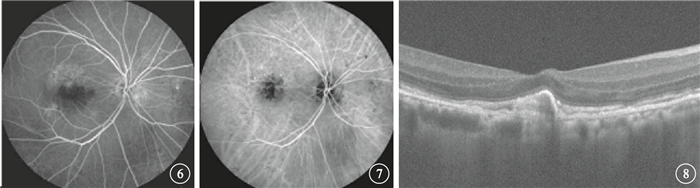

治療后1、3、6個月及末次隨訪時,患眼平均CRT分別為(284.25±66.12)、(295.05±104.17)、(256.00±64.06)、(255.60±55.43)μm,較治療前分別降低了(91.15±122.14)、(80.35±95.01)、(119.40±153.83)、(119.80±155.83)μm,差異均有統計學意義(t=3.34、3.78、3.47、3.44,P<0.05)(圖 5)。

圖5

患眼平均CRT變化趨勢

圖5

患眼平均CRT變化趨勢

治療后1、3、6個月及末次隨訪時,患眼平均CRT分別為(284.25±66.12)、(295.05±104.17)、(256.00±64.06)、(255.60±55.43)μm,較治療前分別降低了(91.15±122.14)、(80.35±95.01)、(119.40±153.83)、(119.80±155.83)μm,差異均有統計學意義(t=3.34、3.78、3.47、3.44,P<0.05)(圖 5)。

圖5

患眼平均CRT變化趨勢

圖5

患眼平均CRT變化趨勢